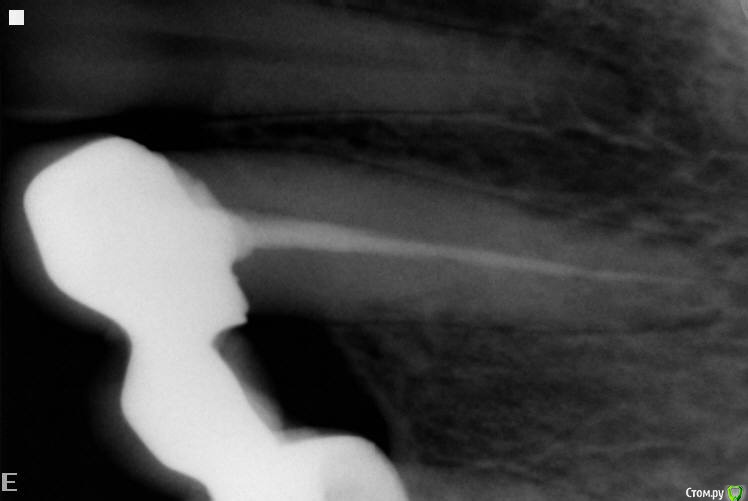

Girl Опубликовано 20 октября, 2016 Поделиться Опубликовано 20 октября, 2016 Сегодня обратилась пациентка с жалобами в обл в/ч слева21,22 интактны, 23 - 25 м/к мост, 26, 27 интактны.Показывает на отсутствующий 25, вроде как боль от туда. Экзостозы есть. Переходная незначительно отечна, пальпация - перкуссия б/б.На 22 контактная полость Подскажите,пожалуйста, что может быть? Ссылка на комментарий

krokomot Опубликовано 20 октября, 2016 Поделиться Опубликовано 20 октября, 2016 Сегодня обратилась пациентка с жалобами в обл в/ч слева21,22 интактны, 23 - 25 м/к мост, 26, 27 интактны.Показывает на отсутствующий 25, вроде как боль от туда. Экзостозы есть. Переходная незначительно отечна, пальпация - перкуссия б/б.На 22 контактная полость Подскажите,пожалуйста, что может быть?В шестерке дырка и кариес корня пятерки, гдеж интактные? Нужны снимки с читаемой переапикальной областью, на счет тройки тоже сомнения, сделайте более качественные снимки, зубов под мостом и смежных с ним зубов 2 Ссылка на комментарий